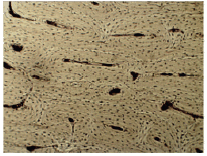

A imagem abaixo representa o tecido ósseo visto em um microscópio óptico com um aumento de 400 x.

Sobre o tecido apresentado na imagem, analise as seguintes afirmativas:

I- É um tecido avascular.

II- Contém células vivas denominadas osteócitos, osteoblastos e osteoclastos.

III- A matriz extracelular contém fosfato de cálcio responsável pela rigidez do osso.